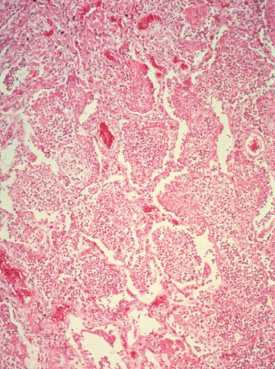

Lobar Pneumonia

Congestion

Red hepatization

Gray hepatization

Resolution